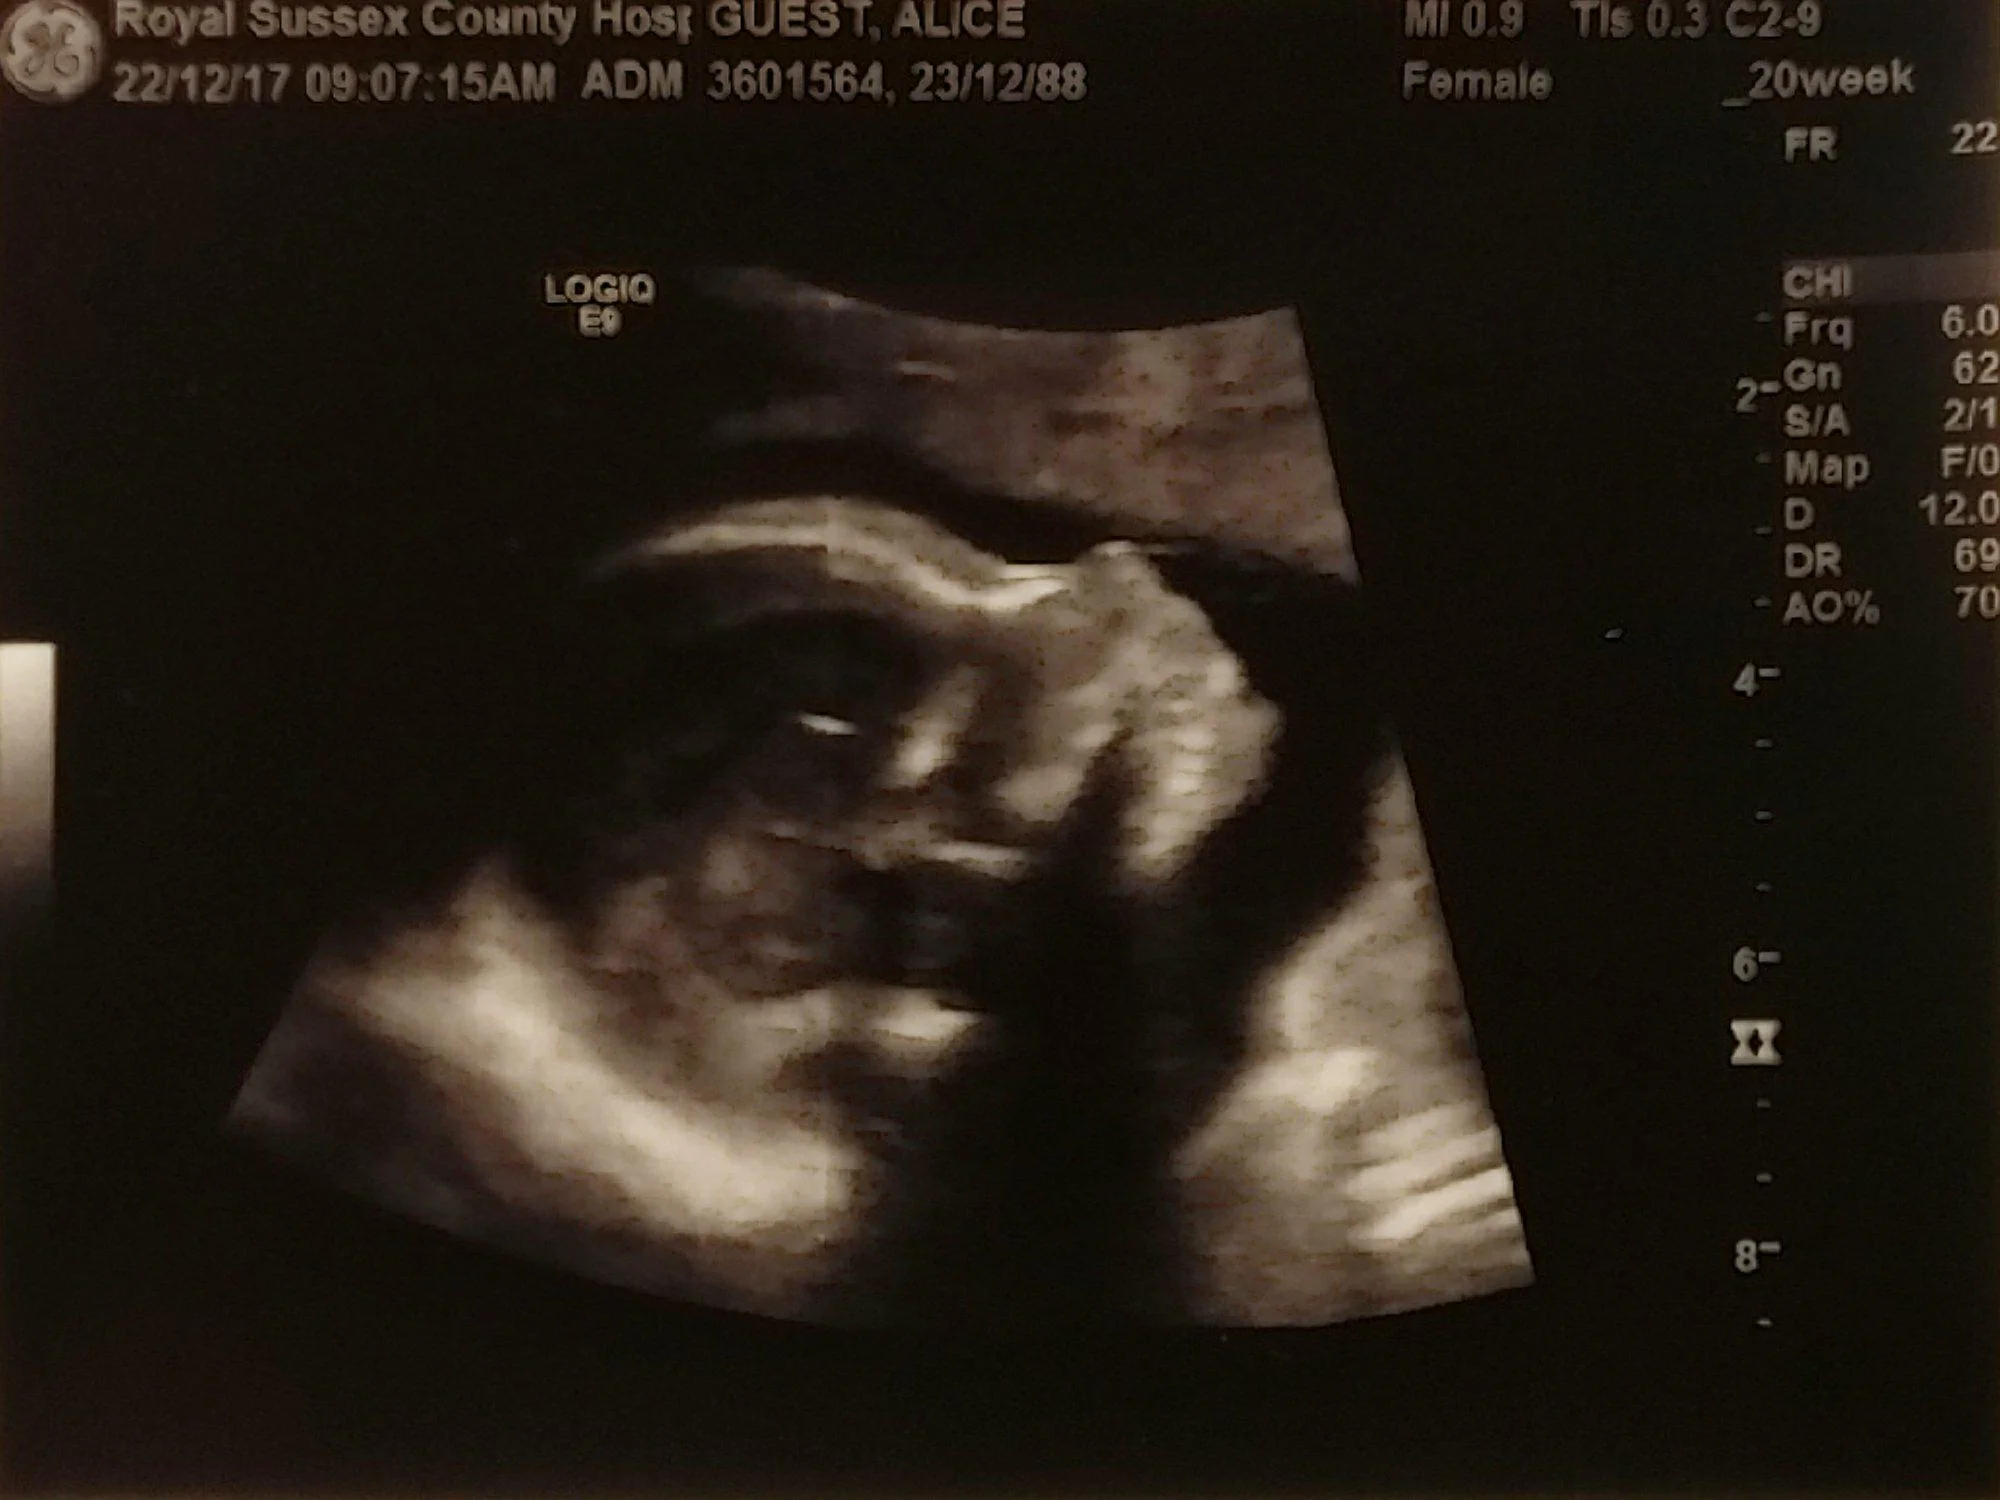

They say you should start to feel your baby move from around 16 to 25 weeks. They also say that if it’s your first pregnancy, you might not feel movements until around 25 weeks. I can't remember the first time I felt our baby move, I found it hard to establish what was movement and what was just my stomach digesting. I think it was around 21 weeks, just after my second scan.